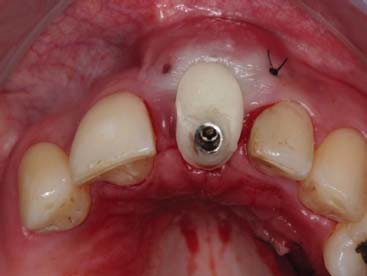

Finalizado toda a parte cirúrgica foi feito o posicionamento de um cilindro provisório e da tampa de cobertura que havia sido confeccionado no gesso e feita a união com resina tipo flow, seguindo do acabamento e polimento fora da boca. Uma vez pronto o cicatrizador personalizado, este foi instalado com o torque de 15N e uma prótese parcial removível provisória foi instalada (figura 9, figura 10, figura 11, figura 12, figura 13 e figura 14).

A paciente retornou após 4 meses e foi constatado um resultado satisfatório da cicatrização tecidual e a manutenção da arquitetura gengival (figura 15 e figura 16).